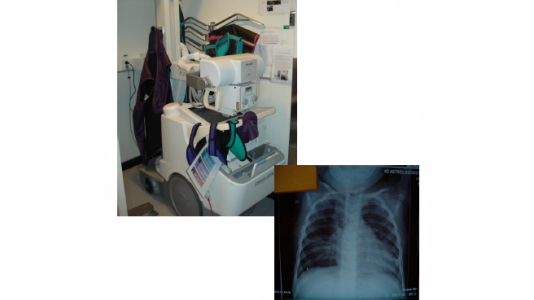

In the list below are explanations for commonly used terms within neonatal care – examination methods, treatments, medical devices and equipment.